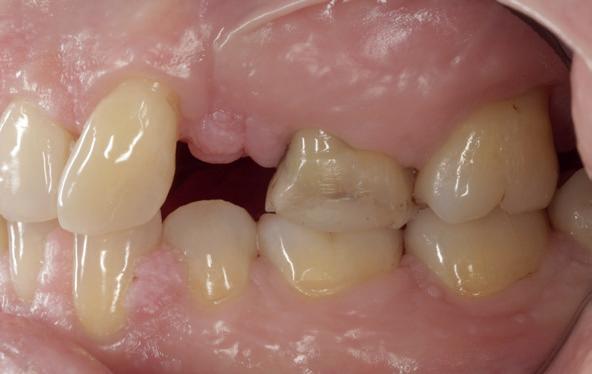

Herstel: terug naar de basis (afbeelding 17-19)

De behandeling van dit mislukte implantaat volgde een stapsgewijze aanpak:

1. Explantatie van het implantaat. Het implantaat werd voorzichtig verwijderd, waarbij ik probeerde zoveel mogelijk bot te behouden.

2. Curettage en reiniging. De alveole werd intensief gecuretteerd en gespoeld tot er geen exsudaat meer aanwezig was. Met goede communicatie kon ik de patiënt overtuigen om 3 maanden later terug te komen voor de botopbouw, zodat we het beste fundament konden creëren voor een duurzame oplossing.

3. Botopbouw met GBR. Ik koos voor een combinatie van allograft, xenograft en autograft om de botdeficiëntie aan te pakken. Dit mixen van bottypes creëerde een optimale omgeving voor regeneratie.

4. Twee-fasen implantologie. Dit keer nam ik geen risico’s. In plaats van een immediaat implantaat koos ik voor een delayed plaatsing. Het bot kreeg eerst de tijd om te rijpen voordat ik een nieuw implantaat plaatste. Deze keer verliep de procedure zonder problemen. Het bot herstelde zich zoals verwacht en na enkele maanden kon ik een nieuw implantaat plaatsen, met een correcte osteotomie en zonder onnodige compressie.